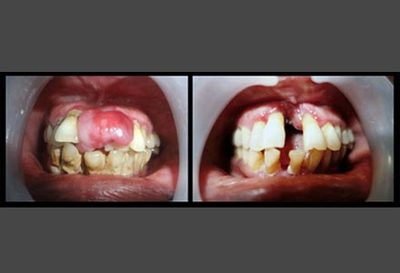

Язвенный гингивит

Воспаление тканей десны, вместе с которым происходит эрозия, изъязвление и некроз десневого края.

Фото 1. Язвенный гингивит обычно причиняет пациентам резкую болезненность десны на фоне имеющегося воспаления.

Симптомы воспаления:

- резкая боль, затрудняющая приём еды;

- наличие неприятного запаха изо рта;

- отёк, кровоточивость дёсен;

- образование на дёснах язв;

- повышенная температура тела;

- общее недомогание.

Важно! Чаще всего язвенный гингивит образуется у людей 18 – 30 лет. Как правило, протекает остро, но при определённых условиях может перейти в подострую или хроническую форму, в язвенный стоматит и пародонтит.